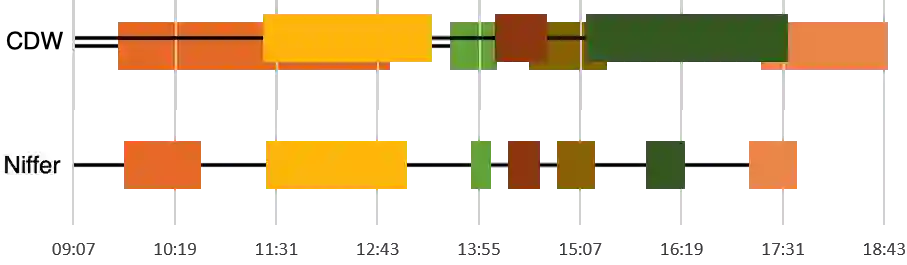

Executing machine learning (ML) pipelines in real-time on radiology images is hard due to the limited computing resources in clinical environments and the lack of efficient data transfer capabilities to run them on research clusters. We propose Niffler, an integrated framework that enables the execution of ML pipelines at research clusters by efficiently querying and retrieving radiology images from the Picture Archiving and Communication Systems (PACS) of the hospitals. Niffler uses the Digital Imaging and Communications in Medicine (DICOM) protocol to fetch and store imaging data and provides metadata extraction capabilities and Application programming interfaces (APIs) to apply filters on the images. Niffler further enables the sharing of the outcomes from the ML pipelines in a de-identified manner. Niffler has been running stable for more than 19 months and has supported several research projects at the department. In this paper, we present its architecture and three of its use cases: an inferior vena cava (IVC) filter detection from the images in real-time, identification of scanner utilization, and scanner clock calibration. Evaluations on the Niffler prototype highlight its feasibility and efficiency in facilitating the ML pipelines on the images and metadata in real-time and retrospectively.